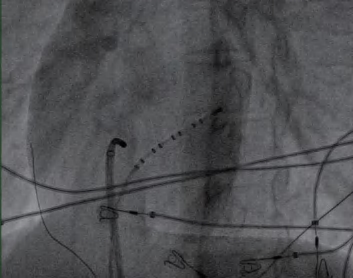

(2)常规选择股静脉穿刺两次或三次,分别置入四极标测电极导管至右心室(图2-2-1)、十极标测电极导管至冠状窦(图2-2-2),必要时再放置四极标测电极导管至希氏束;或者先穿刺一侧股静脉,再穿刺一侧颈静脉或锁骨下静脉作为放置标测电极的入路。

图2-2-1 电极导管置入右心室